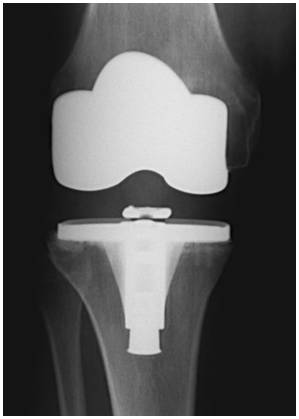

Rango de movilidad y resultados funcionales en tres diseños diferentes de artroplastia de rodilla primaria. Estudio Comparativo. [Range of motion and functional results in three different designs of total knee arthroplasty].